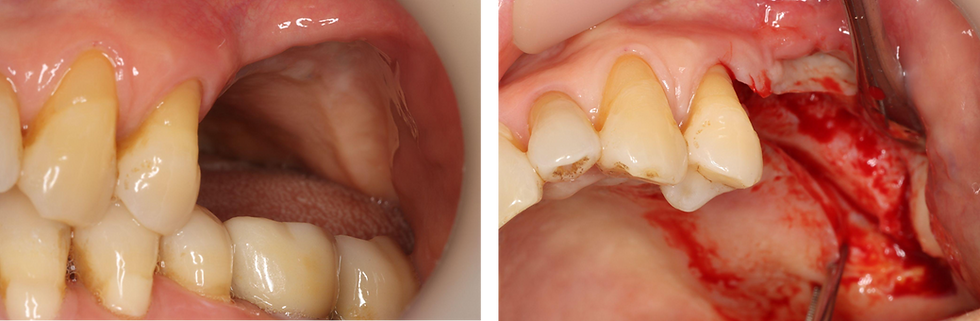

Using a bur to section and remove the existing prosthesis around #25-27 in preparation for fixture removal

After bridge removal, the remaining abutments on #25-27 are exposed

5 months after grafting, the edentulous area shows stable soft tissue healing with adequate keratinized gingiva

A full-thickness flap was elevated to expose the alveolar ridge at the #25-27 area. The grafted bone appears well-maintained with sufficient ridge width and height